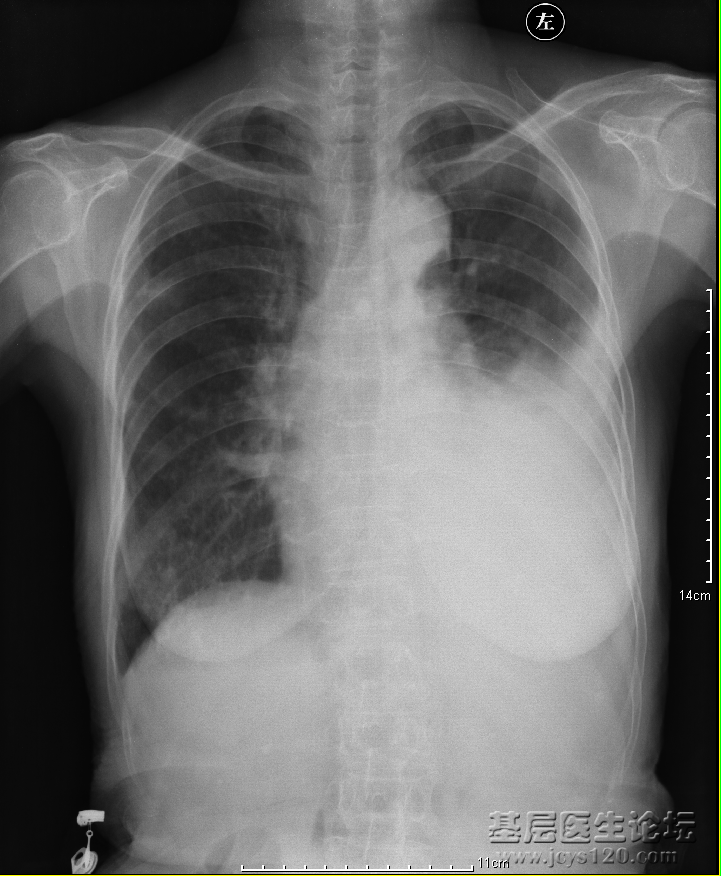

患者:女,78岁,咳嗽咳痰一周,于诊所输液治疗(药物未知)病情时好时坏,现已呼吸困难来本院就诊。 胸部正位: 胸部侧位: 诊断报告: 两侧胸廓对称,气管上纵隔剧中。左肺野缩小约二分之一,下缘 ... 阅读全文>

患者,男,73岁,一年前左侧胸痛伴呼吸困难,现有气喘,心悸,胸痛,发热等 阅读全文>